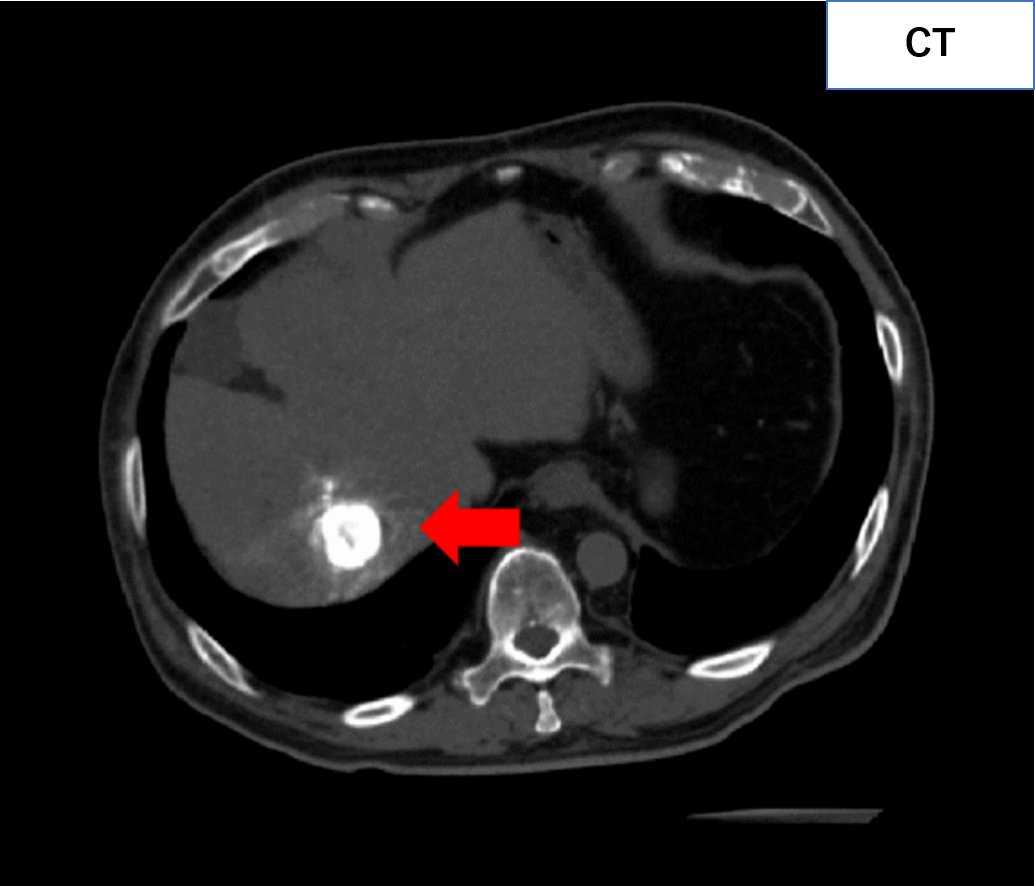

通常のCT画像(下図左)では、正常な組織(臓器や血管など)と病気の「差」が小さく、病気を見つけにくいケースが存在します。静脈から造影剤を注入することで臓器・血管をより明瞭に描出し、病気を見つけやすくすることができます。(下図右の赤矢印)。

単純CTでは見つけられない病気(肝腫瘍)を造影CTで発見!

造影剤を用いて撮影すると、臓器や血管の3次元画像を作成することができます。3次元画像では、あらゆる角度から立体的に観察することができ、診断・治療に用いられています。